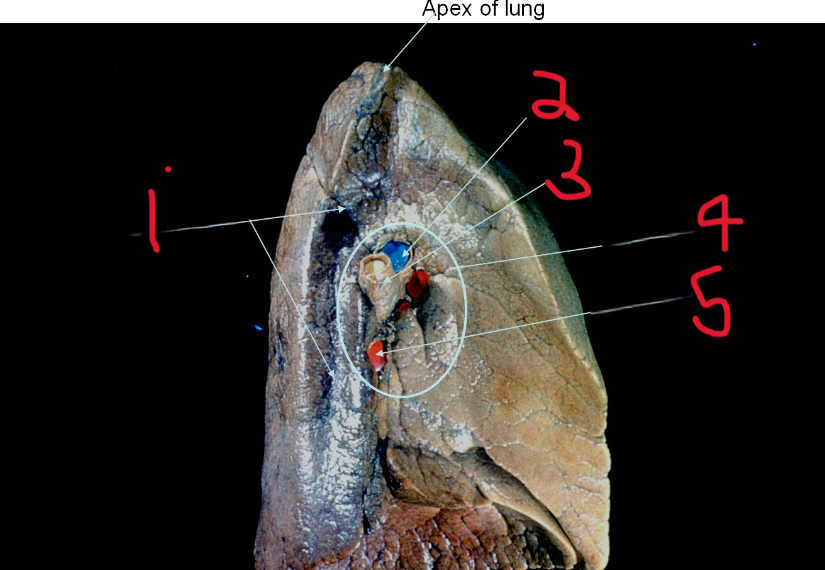

Aortic impression

What is depicted by #1

Pulmonary artery

What is depicted by #2

Left main bronchus

What is depicted by #3

Hilum of lung

What is depicted by #4

Pulmonary vein

What is depicted by #5